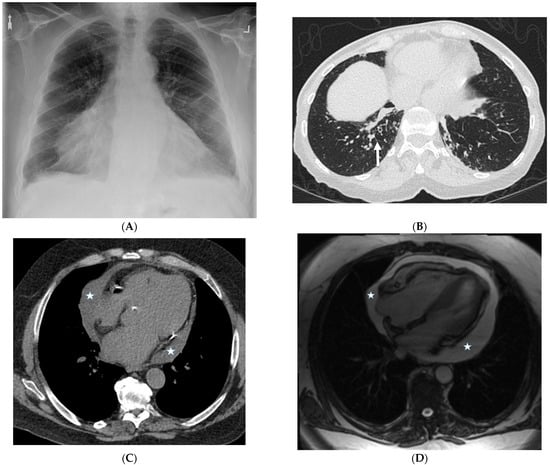

4.7. Pulmonary Vein Stenosis (PVS)

| Pulmonary amyloidosis | Secondary amyloidosis accompanying a chronic inflammatory suppurative process can be related to tuberculosis, bronchiectasis, rheumatoid arthritis, or osteomyelitis. | Multiple intracranial hemorrhages, hepatosplenomegaly, global subendocardial or transmural late gadolinium enhancement on cardiac MRI |